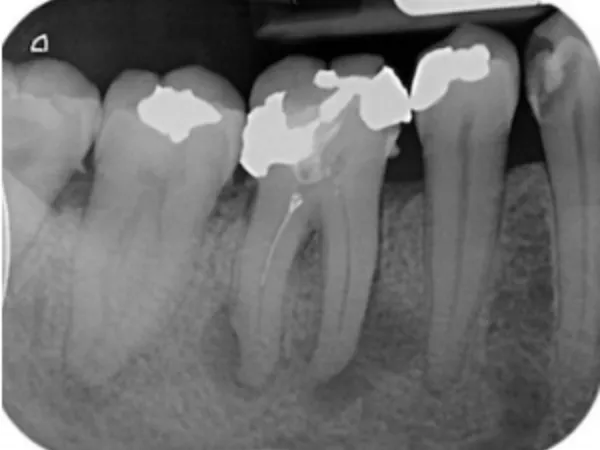

درمان ریشه یا اندودانتیکس یکی از حساسترین و تخصصیترین خدمات دندانپزشکی است که در کلینیک نیکا توسط متخصصین مجرب و با استفاده از تجهیزات دیجیتال پیشرفته انجام میشود. این درمان زمانی انجام میشود که پالپ دندان (بافت نرم داخل ریشه) دچار التهاب یا عفونت شده باشد. در کلینیک نیکا، مراحل درمان شامل تصویربرداری دقیق با دستگاههای دیجیتال، بیحسی موضعی بدون درد، پاکسازی کامل کانالهای ریشه و پرکردن آنها با مواد زیستسازگار است. استفاده از لوپهای بزرگنمایی و فایلهای روتاری باعث افزایش دقت و کاهش احتمال شکست درمان میشود

در این فرآیند، دندانپزشک با استفاده از ابزارهای تخصصی، پالپ آلوده را خارج کرده Pulpectomy، کانالهای ریشه را پاکسازی و ضدعفونی میکند Canal Disinfection، سپس آنها را با مواد پرکننده مخصوص مانند گوتاپرکا (Gutta-Percha) مهر و موم مینماید. در بسیاری موارد، برای افزایش دوام و عملکرد، از روکش دندان Dental Crown استفاده میشود.

اگر درمان بهدرستی انجام شود و بیمار بهداشت دهان و دندان را رعایت کند، دندان عصبکشیشده میتواند سالها بدون مشکل باقی بماند. استفاده از روکش پس از درمان نیز به افزایش دوام و استحکام دندان کمک میکند.